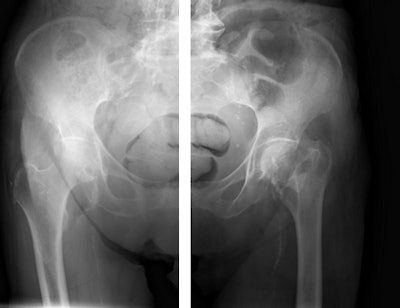

Pelvic radiographs taken with and without SkyFlow scatter suppression algorithm. Image courtesy of Philips.